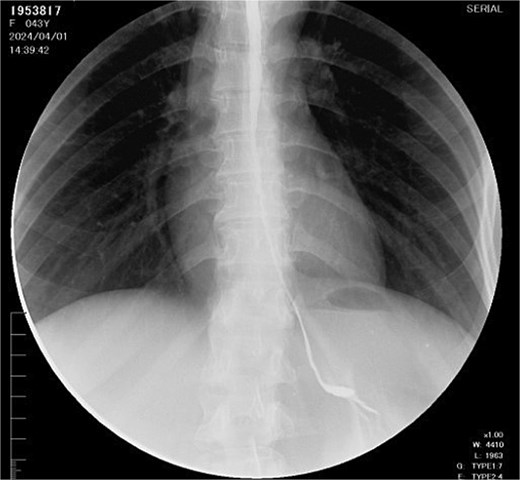

The right colon was mobilized using a standard Cattell–Braasch maneuver. Intraoperative assessment revealed the absence of the right colic artery; perfusion relied on the ileocolic artery and the right branch of the middle colic artery via a well-formed marginal artery of Drummond (Fig. 2). Temporary occlusion of the ileocolic vessels confirmed adequate collateral flow (Fig. 3). The terminal ileum was transected ~3 cm proximal to the ileocecal valve, and an incidental appendectomy was performed.

Confirmation of collateral vascular flow in the right colon (arrow shows ileocolic artery).